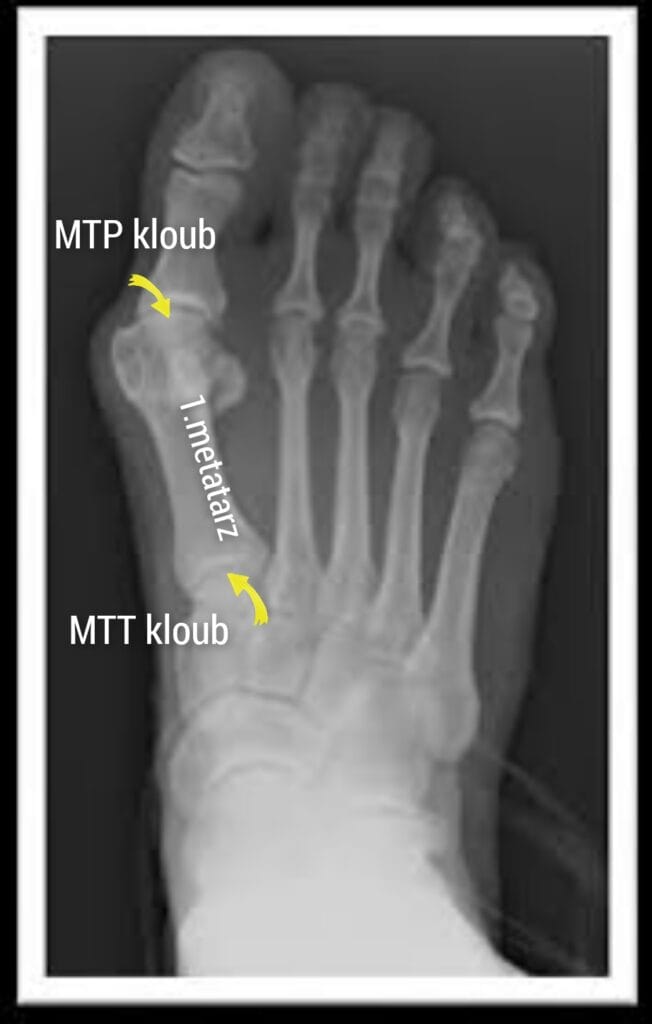

Vbočený palec, také známý jako hallux valgus, je kostěný výrůstek na vnitřní straně nohy v blízkosti kloubu palce. Tvoří se, když se dlouhá kost nohy nazývaná 1. metatarz posune z místa kvůli nestabilitě středonoží nebo laxitě(uvolnění) vazů.

Kromě toho, jak se 1. metatarz začíná posouvat ven, je palec přitahován k ostatním prstům malými svaly na spodní části chodidla. Tento protichůdný posun mezi 1. metatarzem a palcem nohy způsobuje ztrátu kongruence kloubních ploch a asymetrické zatížení chrupavky.

Příznaky vbočeného palce se mohou značně lišit v závislosti na velikosti vbočení a stupni subluxace MTP kloubu palce. Lehčí stupeň vbočeného palce se může projevovat tím, že je nám obuv těsná, výstupek u kloubu palce je podrážděný, zarudnutý. Dále se objevuje bolest při extrémní flexi (ohnutí) palce nohy. Zatímco pacienti s těžším stupněm halluxu se můžou potýkat se zánětem kloubu, omezeným rozsahem pohybu palce, bolestí palce kvůli artritidě a palec může tlačit do 2.prstu nebo ho dokonce překrývat.